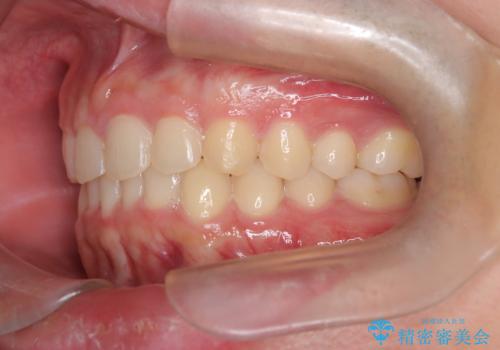

【インビザライン】前歯のガタガタと、前歯の噛み合わせが深いことを治したい。

- 前歯のガタガタと、前歯の噛み合わせが深いことを治したい。との主訴で来院されました。

シミュレーションを用いながら患者様と仕上がりについて相談しインビザラインにて治療を行いました。

仕上げは追加アライナーを数回利用しておこないました。